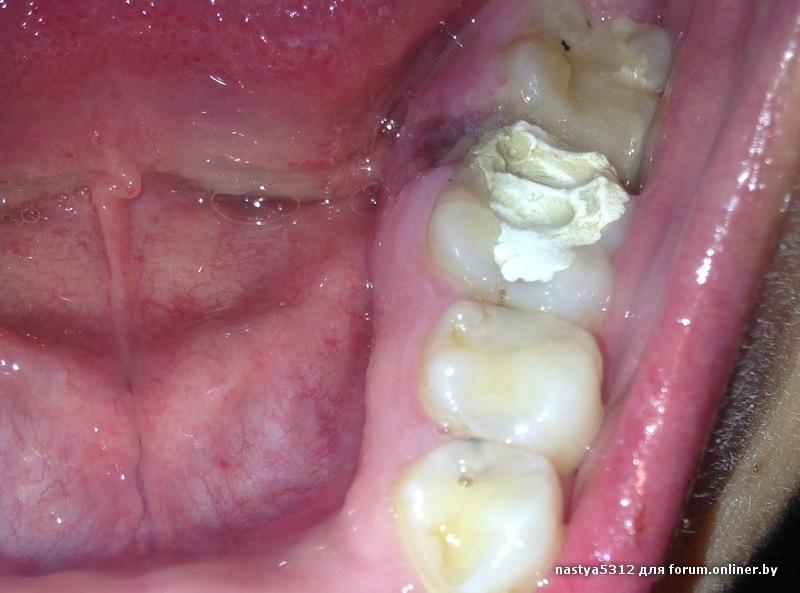

Поставили временную пломбу, в результате сильный отек дёсен, и боль при нажатии на зуб и десна. Фото спустя 4 дня, и с каждым днём картина становится все хуже.кстати весь рот был в пломбе.

Это вообще нормально???

Все зубки в снимке с кариесом! Это нормально? Можно ли было не депульпировать.....? А чем вы думаете пол года ходя с "дуплом"? Кариес наверняка был гораздо раньше чем пол года назад. А потом не говорите что коронку не хотите.